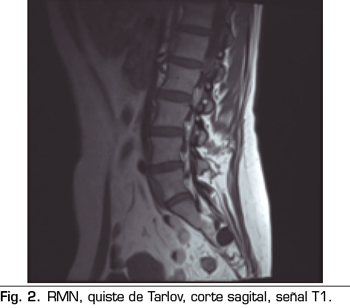

Los “quistes perineurales” o “Quistes de Tarlov” son alteraciones en la duramadre de las raíces nerviosas, que se producen más frecuentemente en la zona sacra. El diagnóstico suele ser casual mediante RMN; la incidencia es variable, debido a que el hallazgo es incidental. Habitualmente son asintomáticos, pero pueden producir radiculopatía, dolor perineal o vejiga neurógena, entre otros.

Figura 2